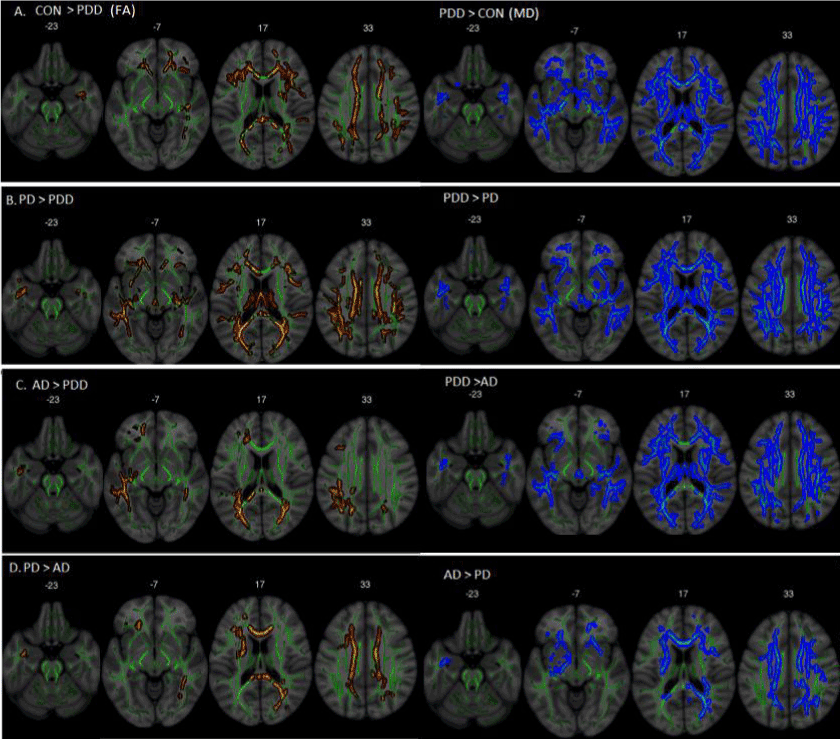

Figure 3: Fractional anisotropy (in red) and mean diffusivity values (in blue). A) PDD showed a higher diffusion compared to controls in the corpus callosum, bilateral posterior inferior fronto-occipital fasciculus, and anterior projections regions. B) Lower diffusion in PDD compared to PD in posterior, anterior, and CC regions. C) AD shows higher diffusion when compared to PDD in the splenium of the CC and bilateral posterior fibers. D) AD showed lower diffusion values when compared to PD mainly in the corpus callosum, posterior right and anterior IFOF. All images are displayed in a Montreal Neurological Institute (MNI) background (in grey) with the mean FA skeleton superimposed (green).